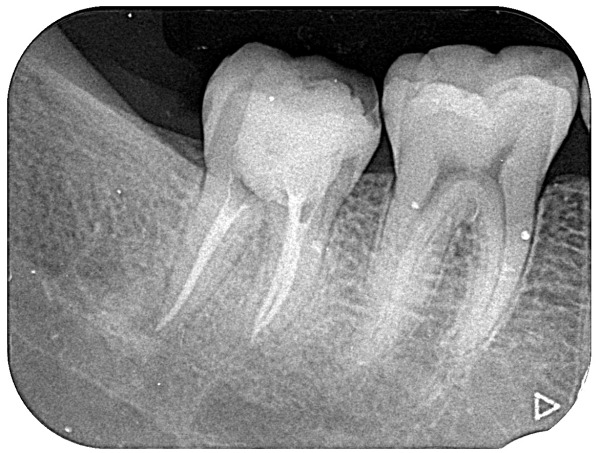

③根管充填

神経を取り除いた空間に綺麗にガッタパーチャというゴム性の材料を充填します。この材料を綺麗に詰めることで、細菌の繁殖するスペースを無くし、また根の先の方に細菌が入り込むことを防ぎます。材料を充填した後、根の先端まで材料が届いているかどうかをレントゲンで確認します。

④築造

根管充填後、お口の中の細菌が根の中に再び入ってこないように接着性のあるレジンでしっかりフタをします。